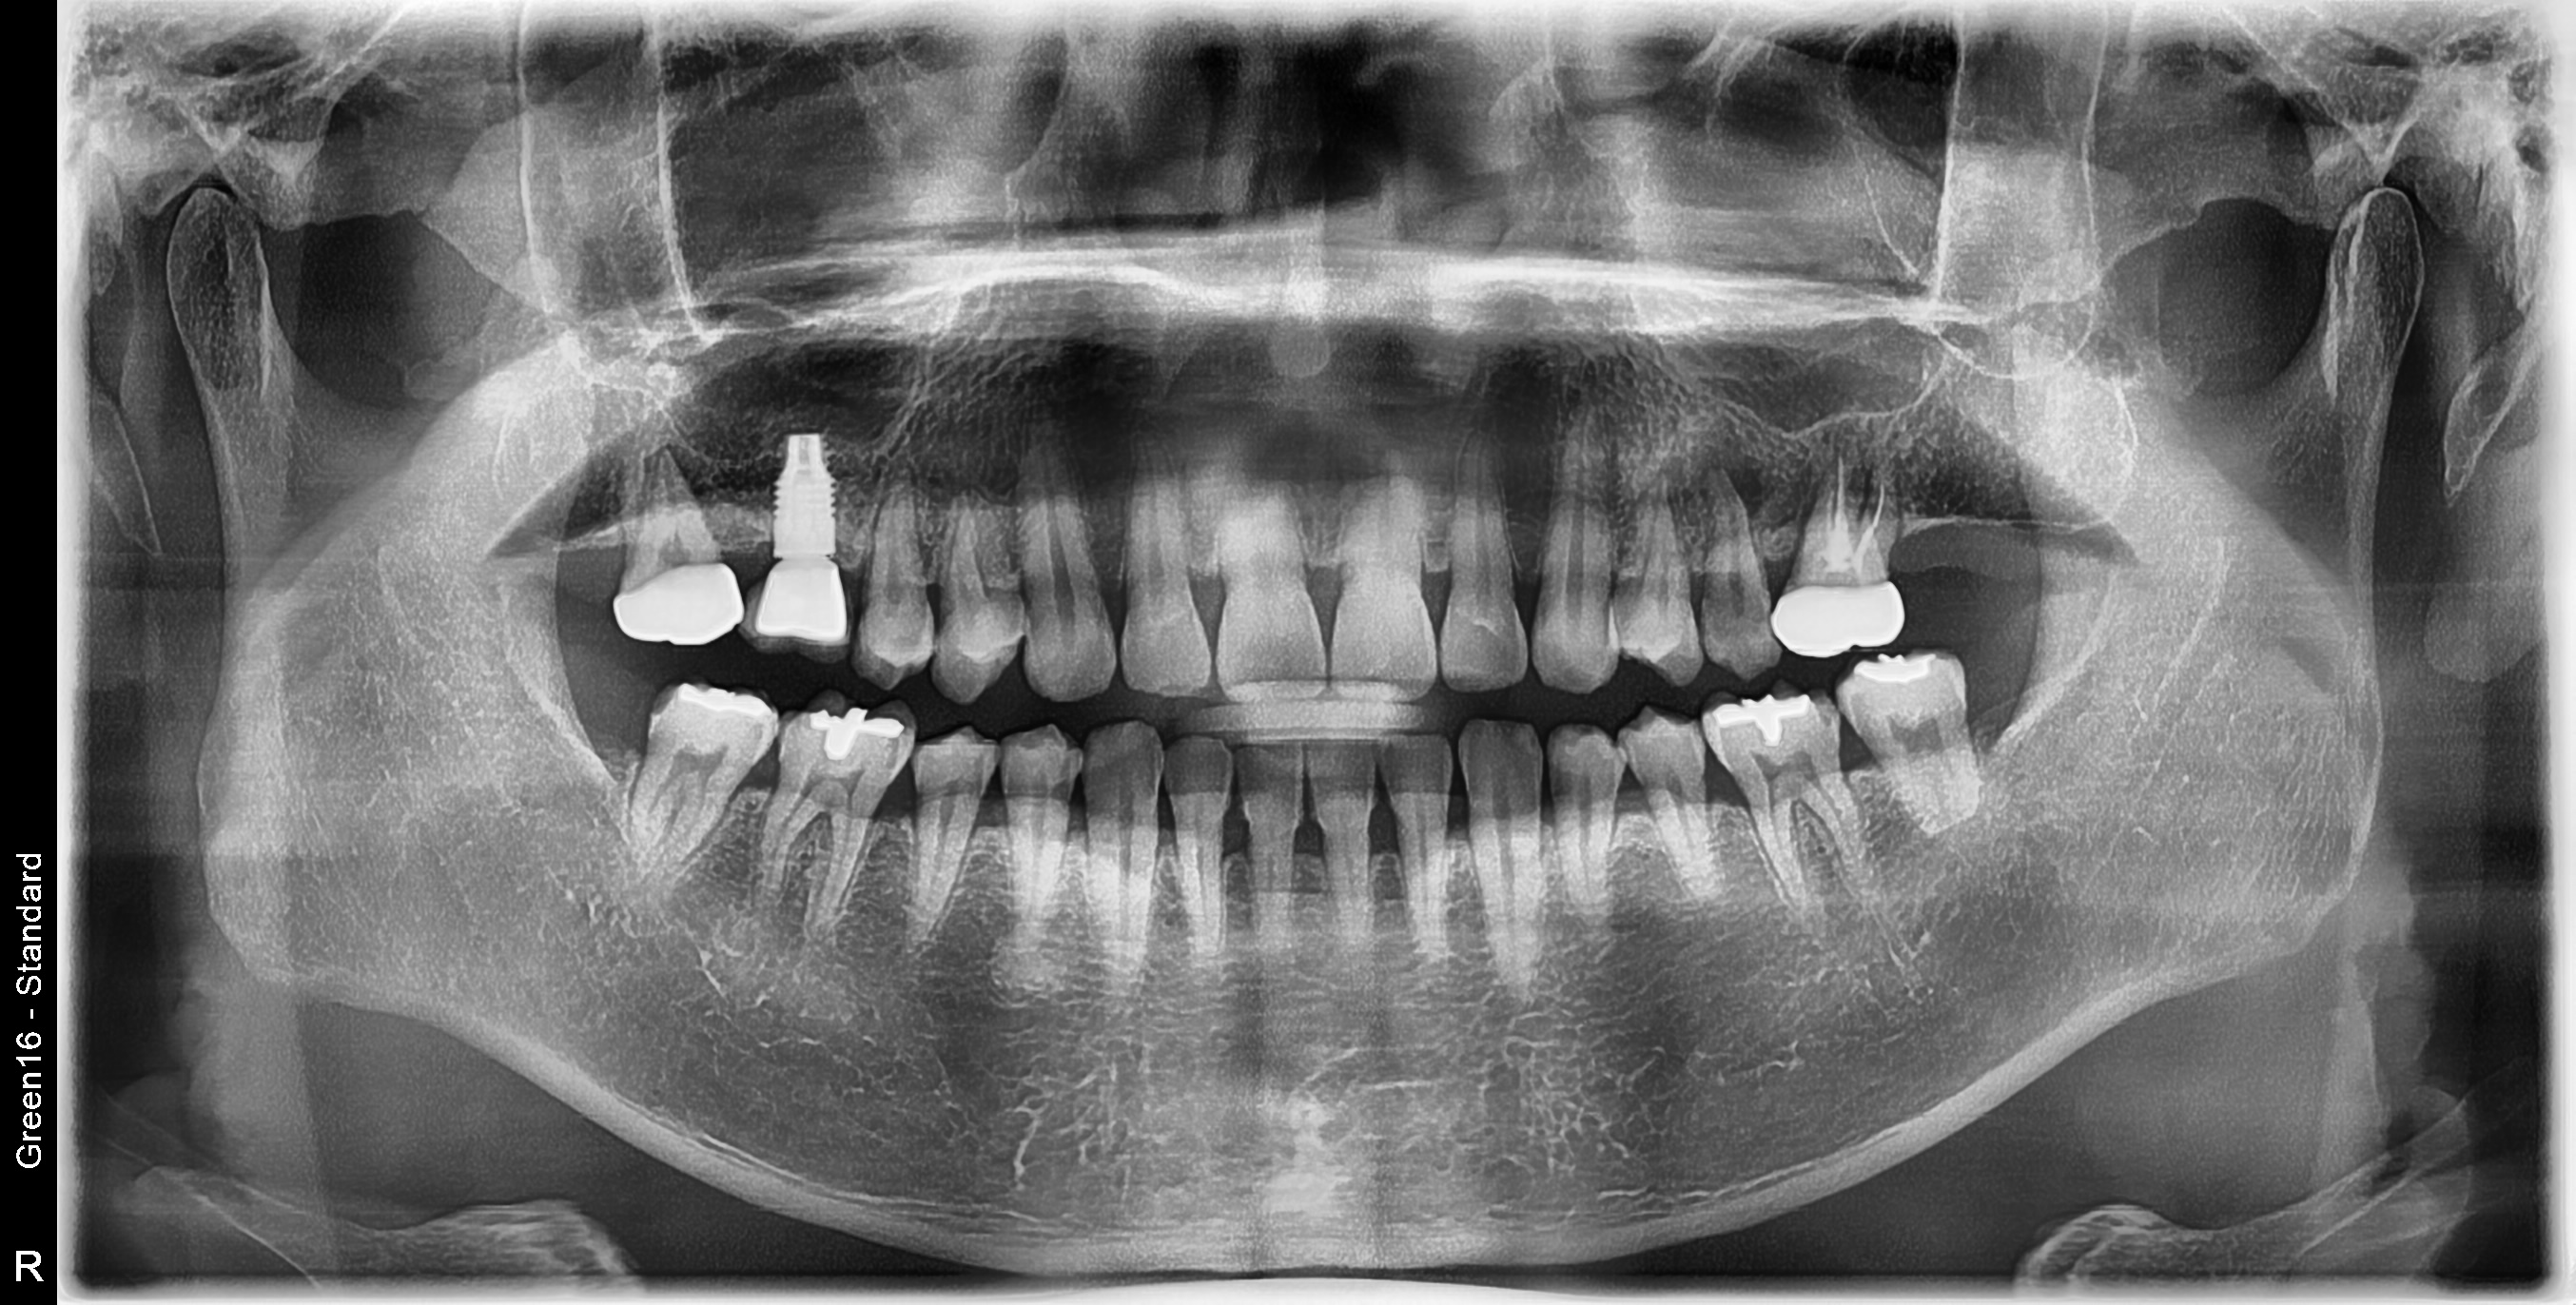

수술 전

수술 후

상악 구치부 식립사례

전후사진